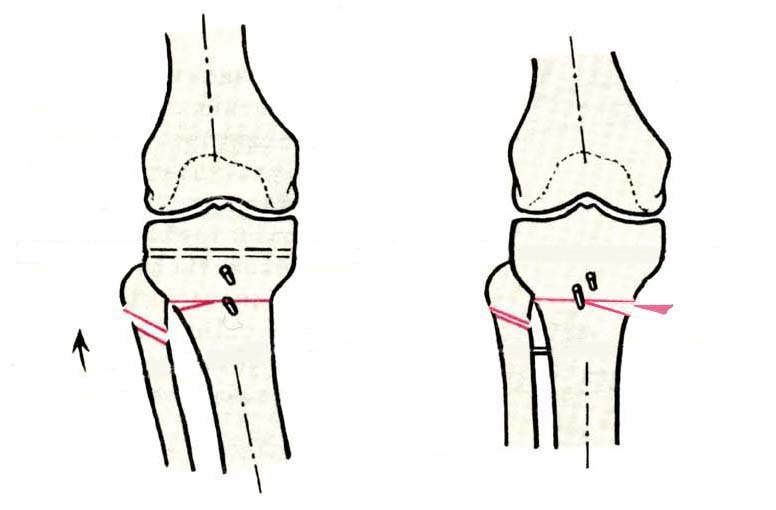

AC> Вот, с учетом и без учета, и на разных уровнях...

Из приведнной схемы не совсеим понял что означают разноцветные линии.

И зачем латерализация периферического фрагмента. Я всегда делаю медиализацию. См схему. И для данного случая медиализация подходит как нельзя лучше.

a> Из приведнной схемы не совсеим понял что означают разноцветные линии.

Черные - это нынешняя механическая ось. Красные - это планируемая правильная ось.

a> И зачем латерализация периферического фрагмента.

;-) Читайте Палея. Стр. 114-115.

a> Я всегда делаю медиализацию. См схему. И для данного случая

Медиализация - это чисто эстетический прием, как я понимаю. Поскольку если делать остеотомию ниже вершины деформации, для восстановления оси надо делать смещение по ширине, в данном случае как раз латерализацию.

А вот на схемке без осей - там на разных уровнях (который правильнее?) устранение варуса чисто открытым клином без медиализации-латерализации. Если как-то так сделать - этого недостаточно будет?